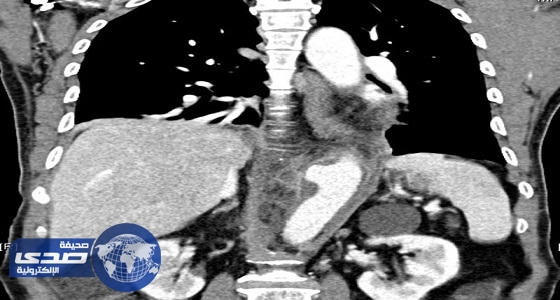

فريق طبي يُنقذ حياة خمسيني ويستبدل شريانه الأورطي بآخر صناعي